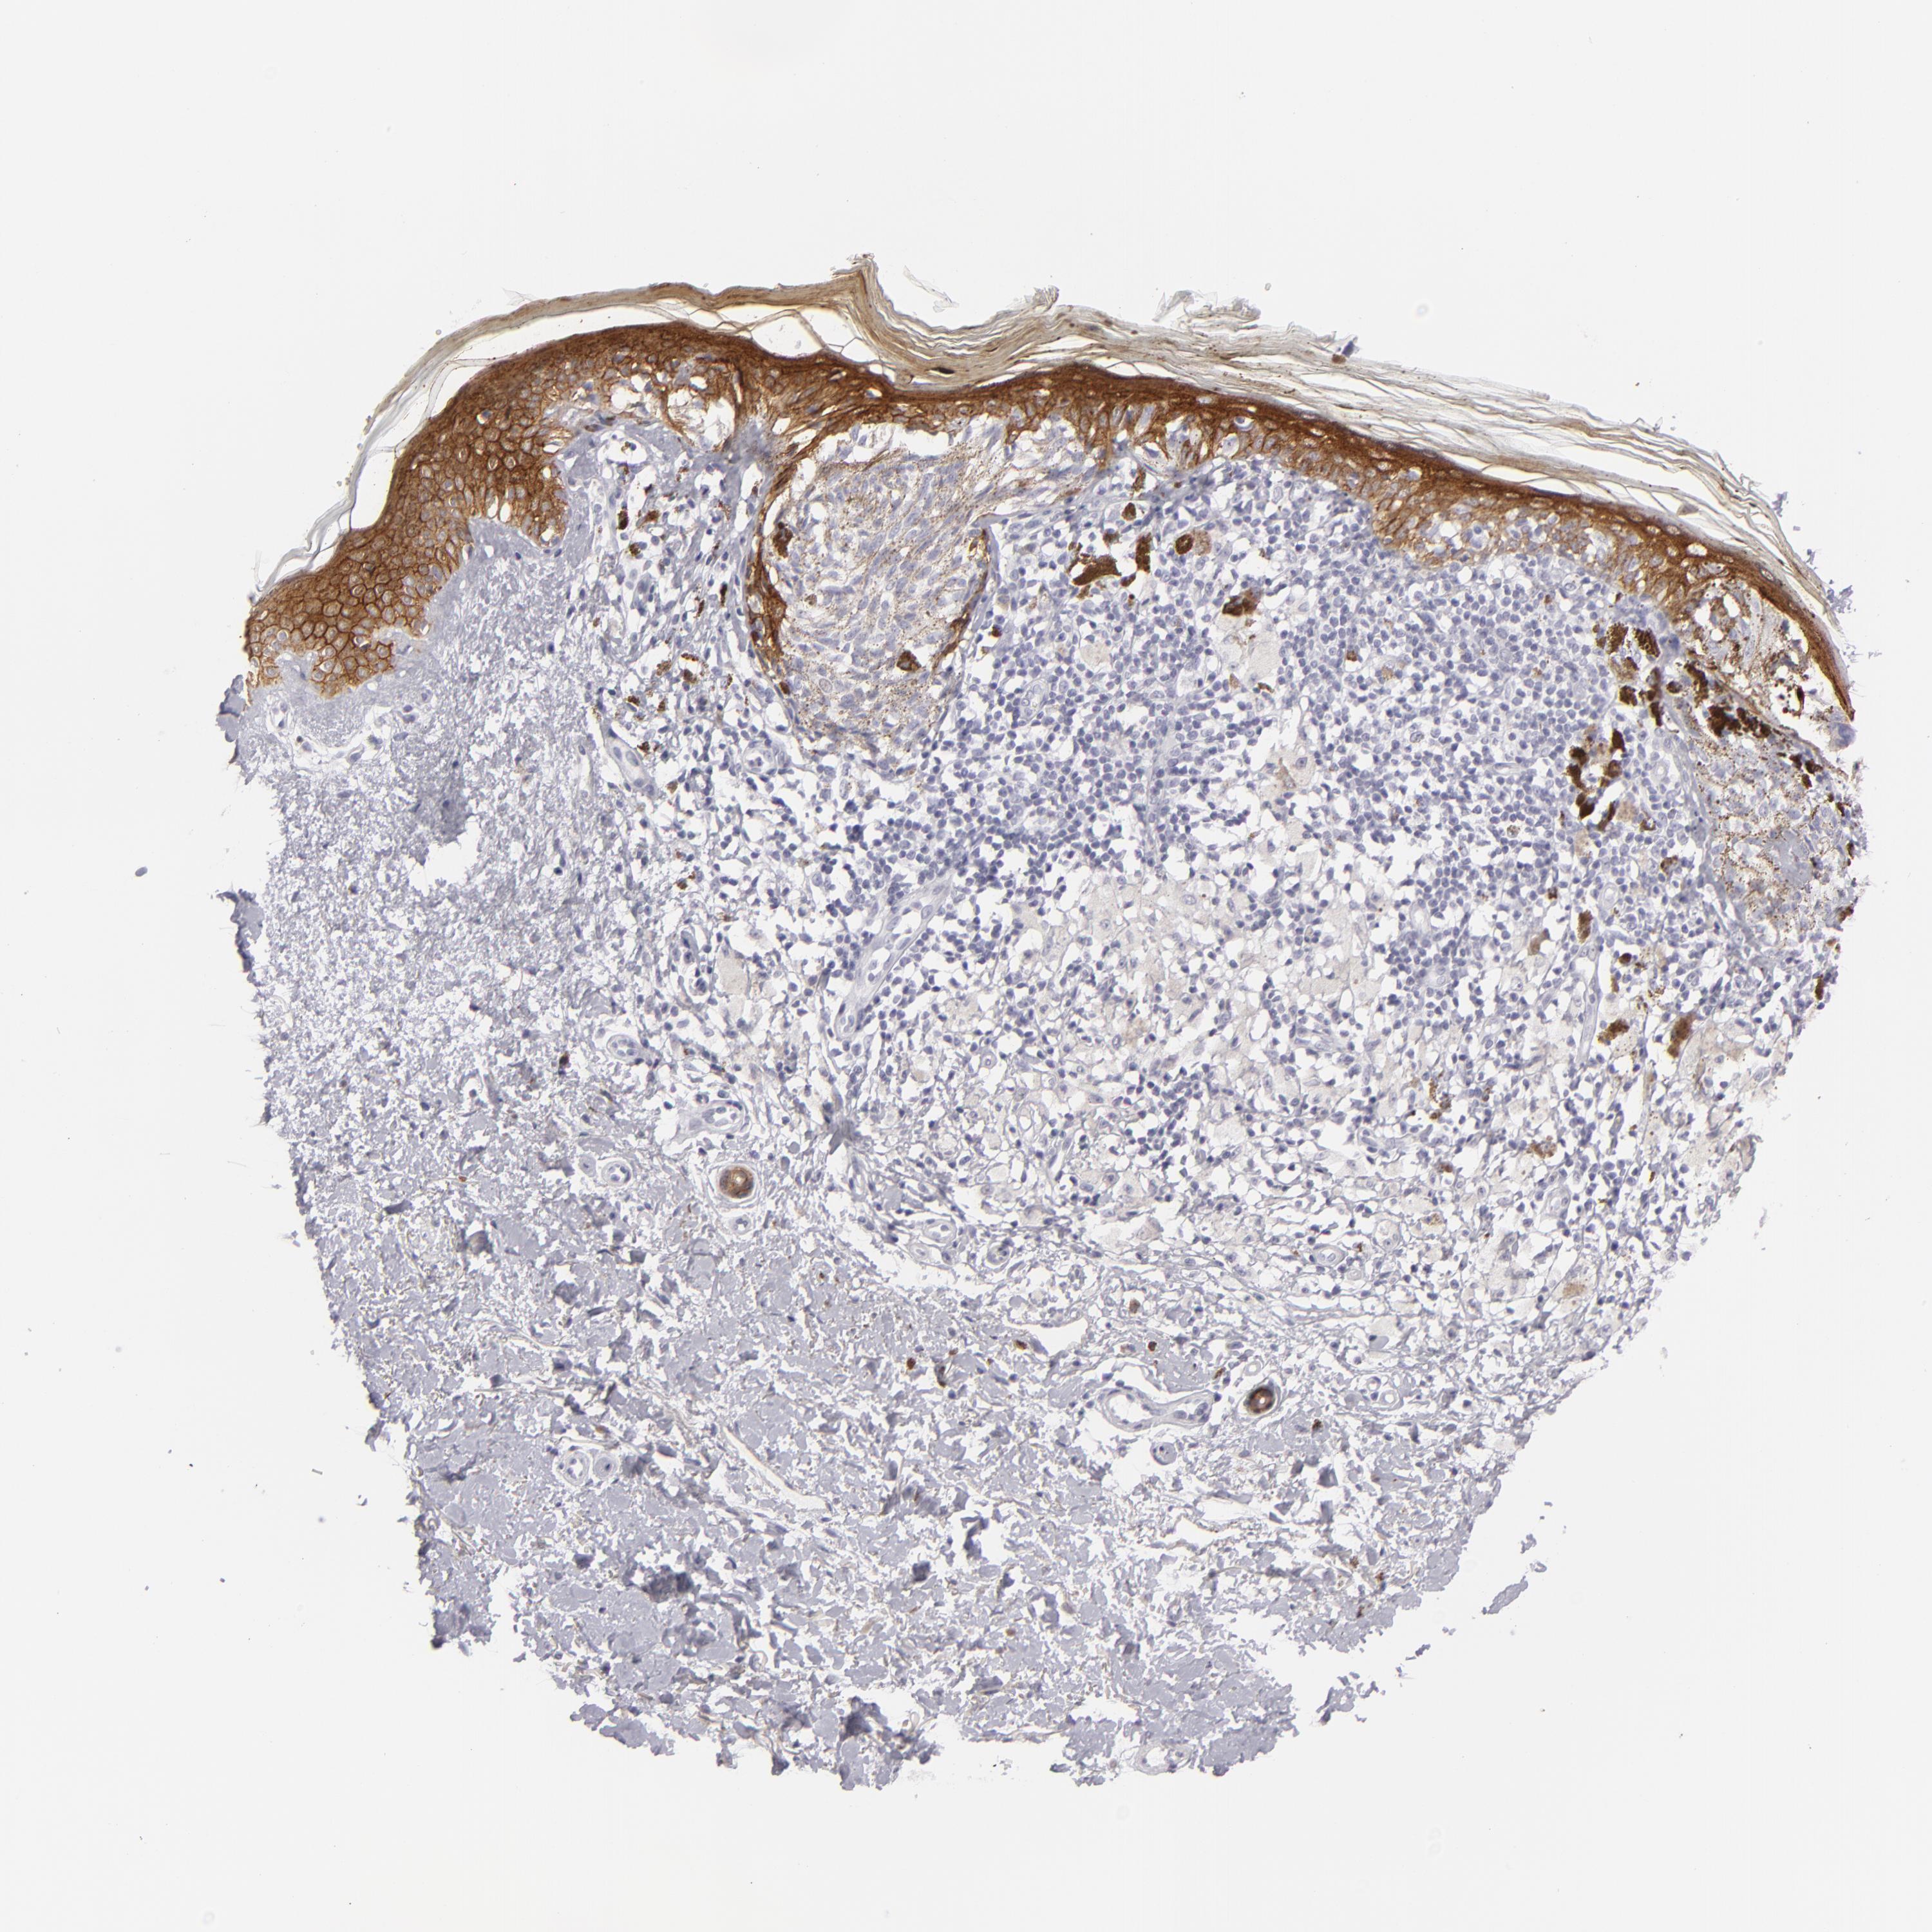

MELANOMA - Protein expressioni

A mouse-over function shows sample information and annotation data. Click on an image to view it in a full screen mode. Samples can be filtered based on level of antibody staining by selecting one or several of the following categories: high, medium, low and not detected. The assay and annotation is described here.

Note that samples used for immunohistochemistry by the Human Protein Atlas do not correspond to samples in the TCGA dataset.

Antibody stainingi

Antibody staining in the annotated cell types in the current human tissue is reported as not detected, low, medium, or high, based on conventional immunohistochemistry profiling in selected tissues. This score is based on the combination of the staining intensity and fraction of stained cells.

Each image is clickable and will lead to virtual microscopy that enables deeper exploration of all samples and also displays staining intensity scores, fraction scores and subcellular localization as well as patient and tissue information for each sample.

Antibody HPA032047

Antibody CAB002139

Staining

High

Medium

Low

Not detected

Intensity

Strong

Moderate

Weak

Negative

Quantity

>75%

75%-25%

<25%

None

Location

Nuclear

Cytoplasmic/membranous

Cytoplasmic/membranous,nuclear

Malignant melanoma, Metastatic site